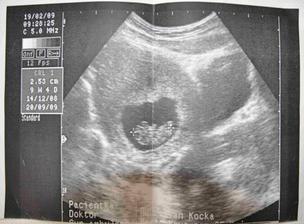

19.2.2009 - KO u Dr. Čeká nás další UTZ a odběry.